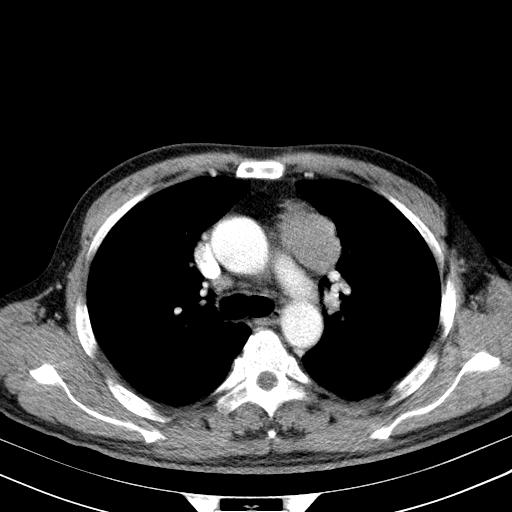

先行ct平扫,纵膈内多发软组织影,ct值约为36hu,以下为增强扫描和腹部平扫。

经典?纵膈多发肿大淋巴结。腹膜后未见异常。

1)考虑淋巴瘤。2)双侧少量胸腔积液。